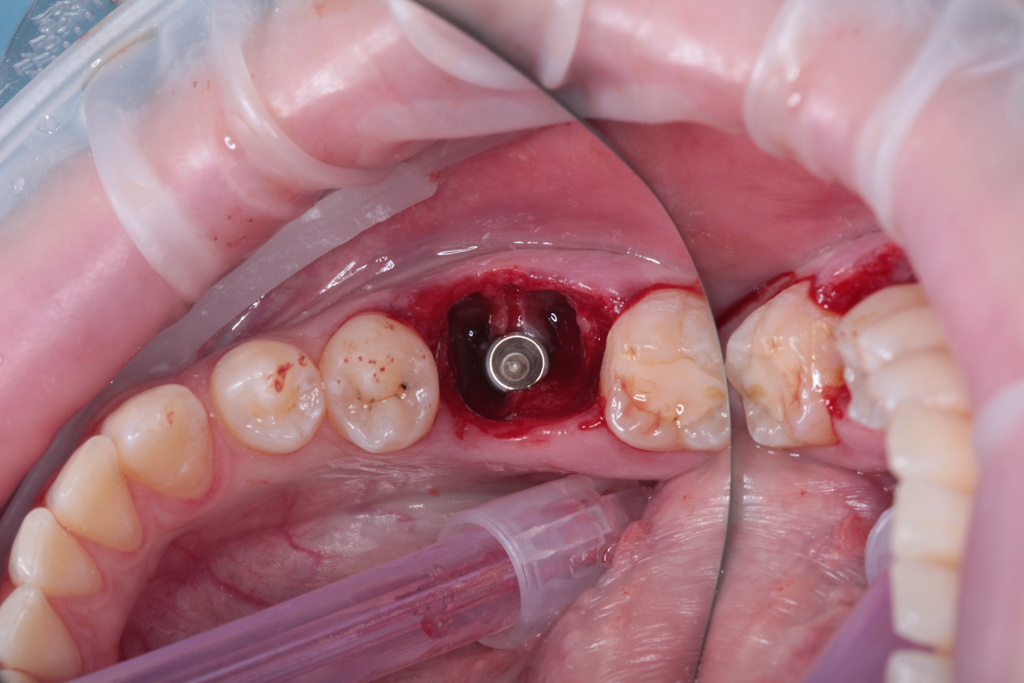

Одномоментная установка дентального имплантата, система Impro